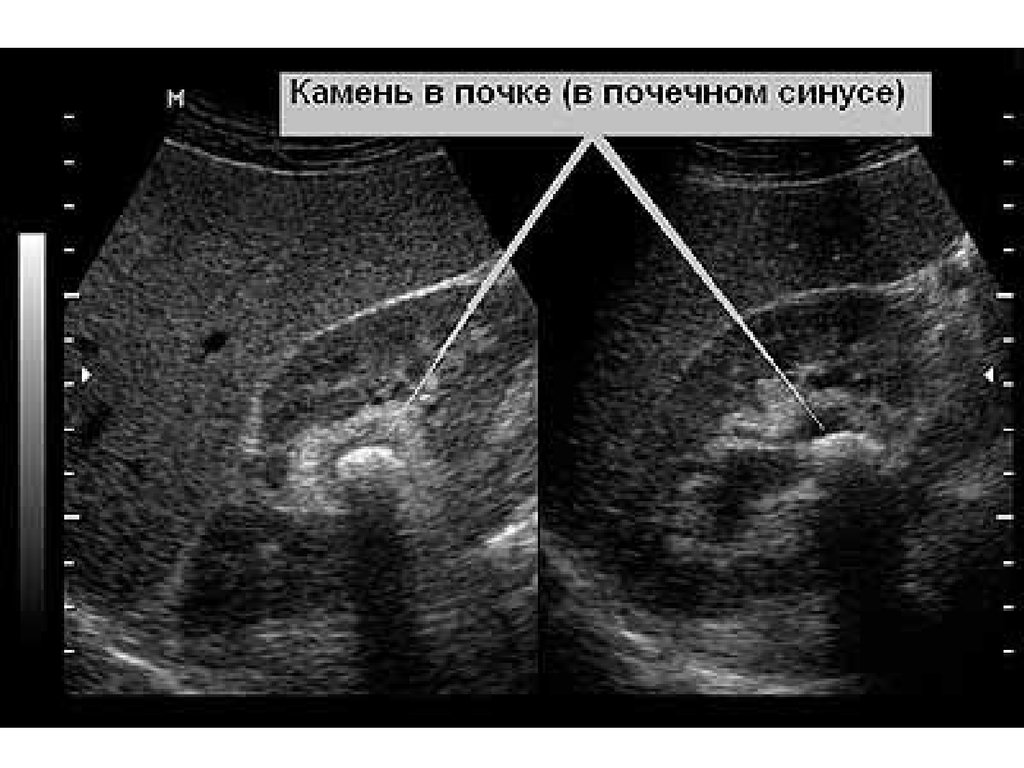

Камни почек

71.

72.